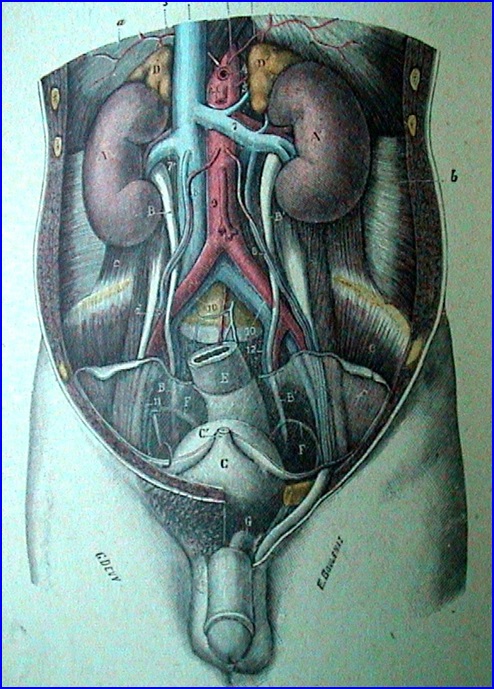

Rinichiul

Organ retroperitoneal, pereche şi simetric, cu formă asemănătoare bobului de fasole.

Dimensiuni şi greutate: depind de statura individului, vârstă, sex şi sunt în medie 12/6/3,5 cm; 140-170g.

Situaţie: de o parte şi alta a coloanei vertebrale, corespunzând vertebrelor T11-T12 superior şi L2-L3 inferior, de-a lungul marginii laterale a m. psoas. Prezenţa ficatului pe partea dreaptă face ca rinichiul drept să fie situat mai jos faţă de cel stâng.

Ureterul

- conduct intermediar între bazinet şi vezica urinară;

- 25-34 cm lungime, calibru inegal, cu strâmtori unde diametrul este de 2-4 mm şi “fuse” unde calibrul este de 5-10 mm;

- 3 stricturi anatomice:

- superioară - la nivelul joncţiunii pielo-ureterale;

- mijlocie - la incrucişarea cu vasele iliace;

- inferioară - la nivelul joncţiunii uretero-vezicale.

VEZICA URINARĂ (la bărbat)

Testiculul

Dimensiuni: 4x3x2,5 cm, formă ovoidă, 20-25 g.

Vascularizaţie:

Arterială:

- a. testiculară (r. din aorta abd.)

- a. deferenţială (r. din a. vezicală inf.)

- a. spermatică ext. )r. din a. epigastrică inf.)

Venoasă:

- vv. testiculare şi epididimare ce se anastomozează formând plexul pampiniform dispus ant. şi post. de funicul® v.testiculară